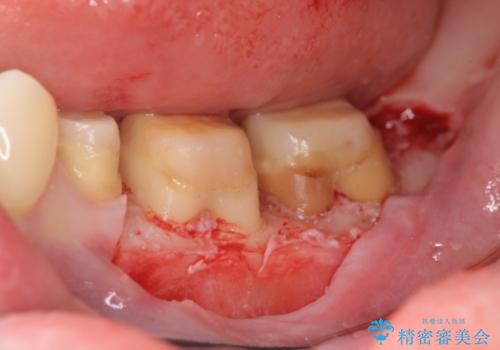

虫歯を除去すると、歯ぐきよりも深い虫歯であることが判明したため歯周外科を行い問題を解決していきます。

歯ぐきの炎症は虫歯や歯周病の再発原因となるため歯周外科による解決が望ましいです。

外科処置の注意事項(リスク・副作用など)

- 外科手術のため、術後に出血、痛みや腫れ、違和感を伴います